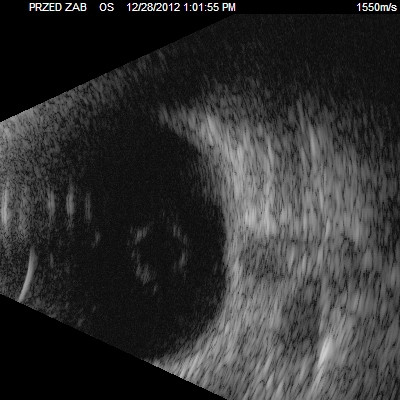

Przedstawiane obrazy ultrasonograficzne® są oryginalne i pochodzą z mojej praktyki lekarskiej